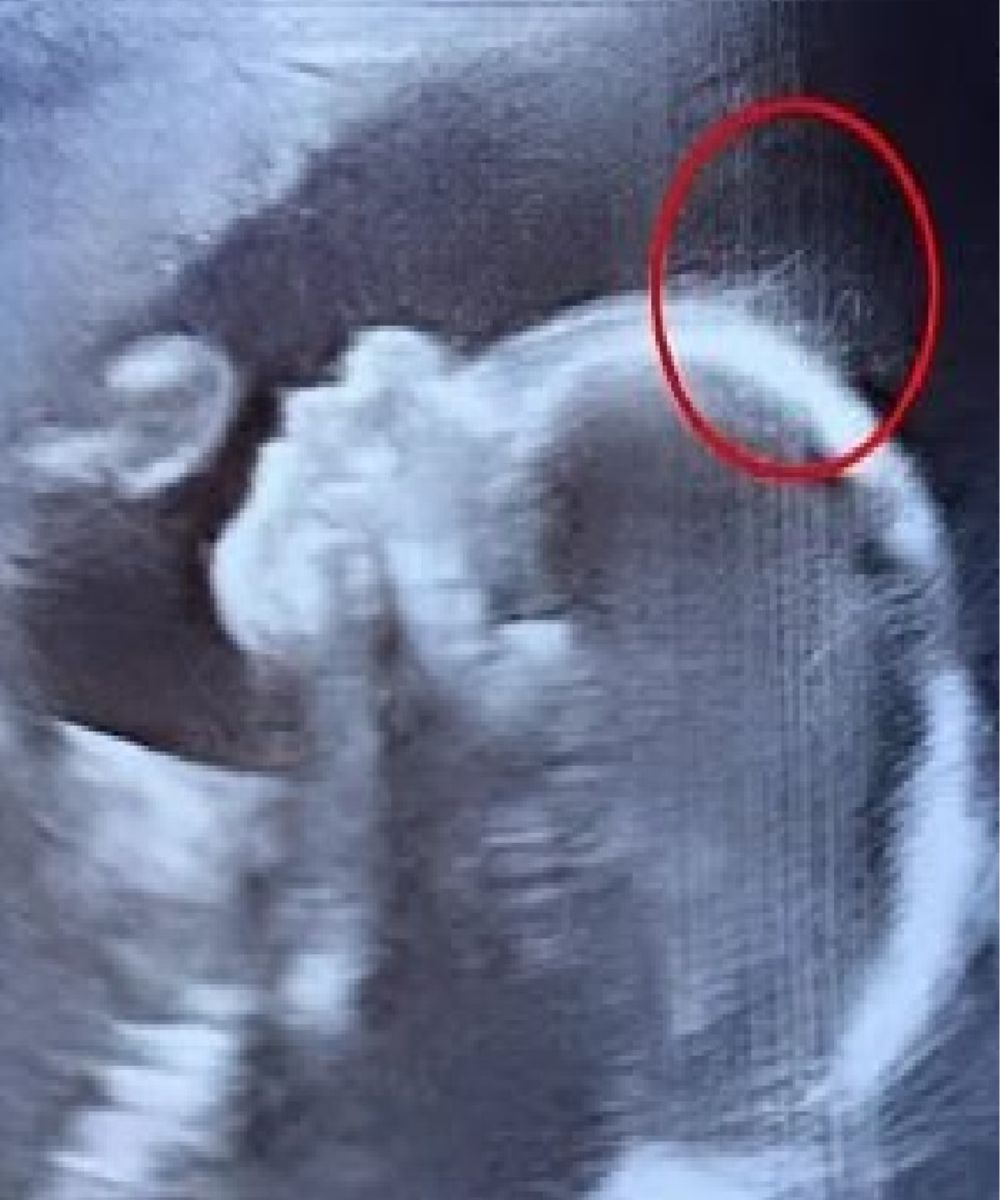

While displaying the ultrasound, the sonographer witnessed the monitor all puzzled, but then she smiled and said, “Wait a minute. Is that hair?” One of the doctors approached closer and said jokingly, “Looks like you’ve got a little rock star in there — she might just skip the baby baldness entirely!”

Indeed, the ultrasound performed wispy strands swaying underwater like seaweed.Some two months later, baby Ivy was born, and her hair was as thick and as long as that of a two-year-old child. The doctors and nurses said they had never seen anything like it before.They also announced to the young mother that children being born with hair wasn’t anything unusual since their hair begins growing in the womb as early as 30 weeks.

What was noticeable was that Ivy’s hair was clear during the scan, and that it was awesome long for a newborn baby.